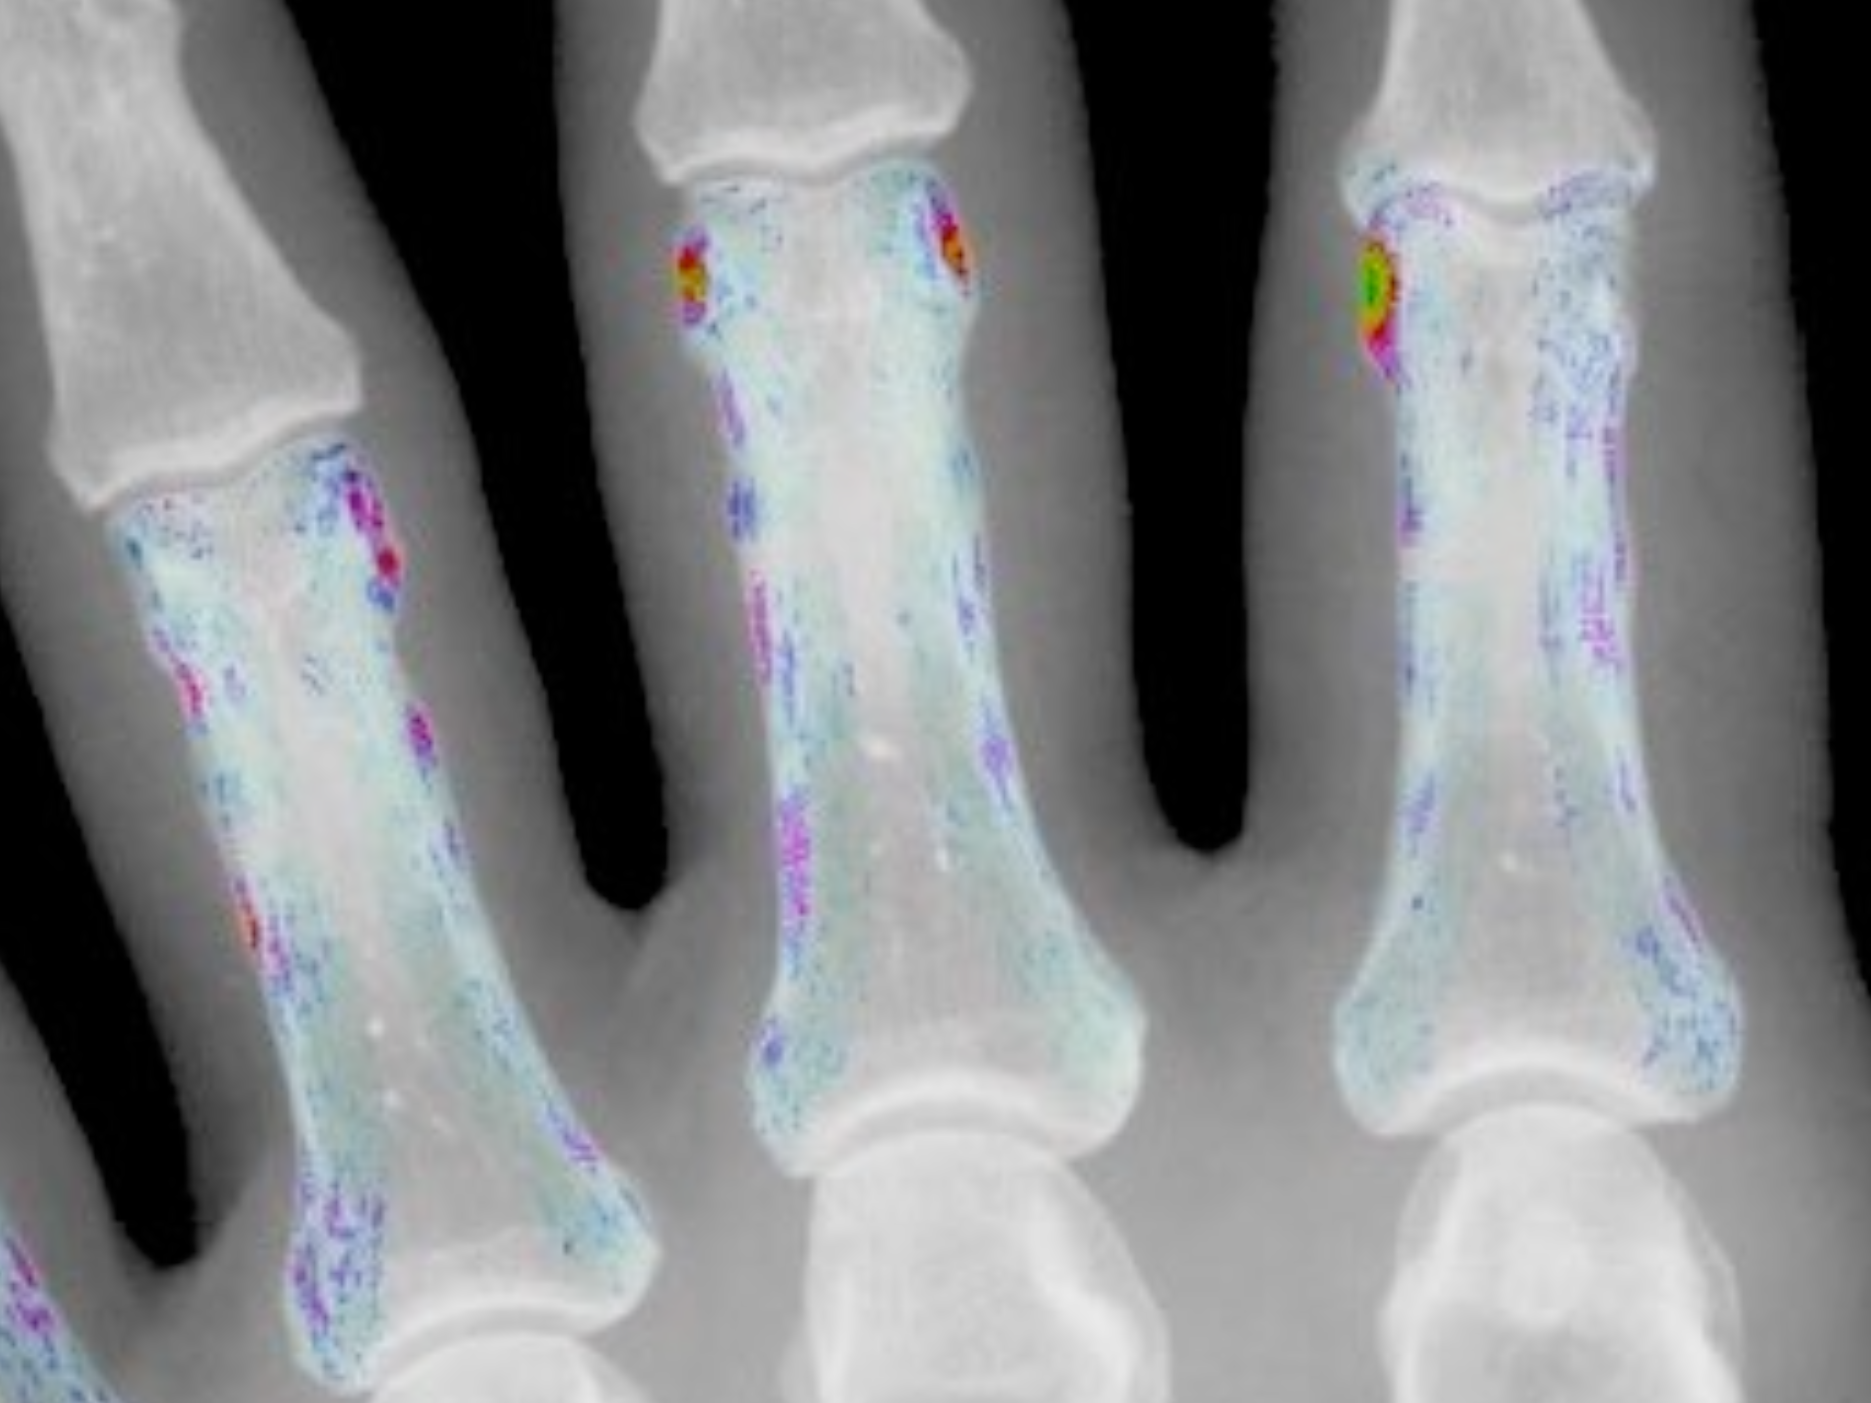

AAMIR

AAMIR - Active Appearance Models in Musculo Skeletal Radiology, funded by the Austrian Science Fund FWF, (2004-2007). The accurate quantification of the progression of rheumatoid arthritis is a decisive factor during its treatment. Until now mainly manual quantification procedures are utilized. They are time consuming and lack reproducibility as well as accuracy. In a project a fully automated method for the assessment of RA is developed.